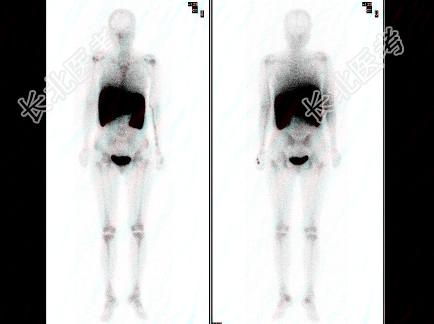

- 多项选择题女性,38岁, 血象三系减少,骨穿两次均干抽, 行

Tcm-PHY骨髓显像,正确的描述是 ( )

A、中心骨髓活性明显受抑

B、外周骨髓活性代偿性扩张

C、骨髓纤维化

D、再障

E、骨髓异常增生综合征